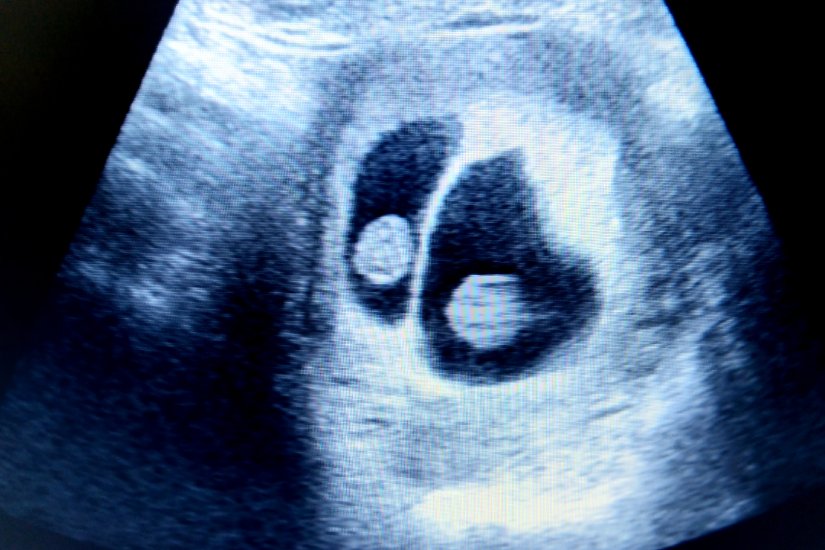

La ecografia de prim trimestru, trebuie să ți se spună dacă gemenii împart placenta sau nu. Toți gemenii care împart placenta sunt identici. Gemenii care au 2 placente separate pot fi identici sau nu. O treime din gemenii identici au placente separate. Acest lucru se întâmplă atunci când oul fertilizat se desparte înainte de implantarea în uter, până la 4 zile după concepție.

Atunci când gemenii nu împart placenta, fiecare geamăn are sac amniotic propriu. Medicii numesc această sarcină dicorionică diamniotică (DCDA). Atunci când gemenii împart placenta, dar nu și sacul amniotic, deci când fiecare geamăn are sac propriu, sarcina se numește monocorionică diamniotică (MCDA). Când gemenii împart atât placenta, cât și sacul, se numește sarcină monocorionică monoamniotică (MCMA).

- Ecografia de confirmare: de obicei, o ecografie realizată între 6 și 8 săptămâni confirmă prezența gemenilor. La 6 săptămâni, pot fi observați sacii gestaționali, iar la 7 săptămâni, bătăile inimii fetale.

La ecografia de gemeni de 8 săptămâni, medicul poate confirma prezența gemenilor, iar fiecare făt va fi vizibil pe ecograf. De asemenea, va fi posibilă evaluarea bătăilor inimii fiecărui făt și examinarea sacilor gestationali- separați pentru gemenii cu două placente diferite ( dicorionici) sau un sac unic pentru cei care împart placenta (monocorionici), oferind informații esențiale pentru planificarea sarcinii.